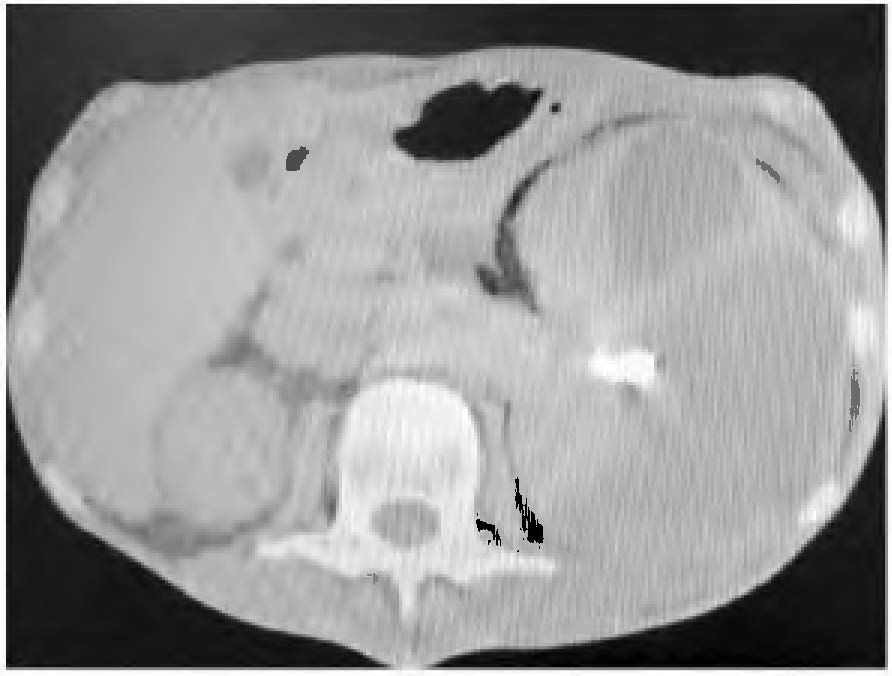

Paciente do sexo masculino, 62 anos de idade, dá entrada na emergência apresentando dor no flanco esquerdo e febre com dois meses de evolução, que se intensificaram na última semana. Realizada tomografia de abdome sem contraste, abaixo representada:

O diagnóstico que se impõe nesse caso é: